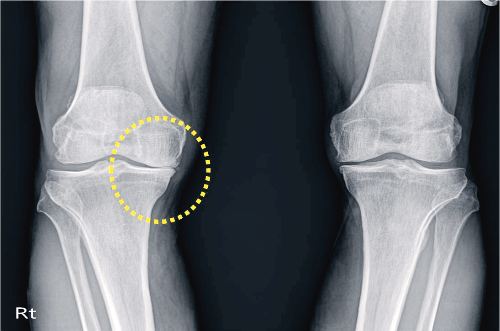

골관절염은 연골에 손상이 가해지면서 관절의 간격이 줄어들고 뼈가 서로 맞닿아 통증을 동반하는 질병입니다. 콘드로이친은 질병과 외부 충격으로부터 체내의 조직을 안전하게 보호하고 동시에 조직 표면에 가해지는 충격 등을 이겨낼 수 있도록 탄성을 주는 프로테오글리칸(Proteoglycan)이라는 물질의 생성을 돕게 됩니다. 때문에 콘드로이친은 특히 골관절염에 효과가 있습니다.

콘드로이틴황산염은 연골 구성 성분의 하나이고 연골세포를 자극해 연골조직을 정상적으로 복원하는데 효능이 있다고 알려져 있습니다. 특히 외부 자극에 의해 문제가 되는 TNF-알파 등 사이토카인의 작용을 억제하는 역할을 합니다. 그리고 지속적인 염증 유발 및 연골 파괴 유발 사이토카인을 감소시켜 관절 내 염증 및 통증반응 그리고 연골파괴를 막아주는데 도움을 줍니다.

콘드로이친은 연골에 보습 및 탄력을 공급하려 상처 난 연골을 정상적으로 재생시키는 효과가 있습니다. 콘드로이친을 섭취하게 되면 무릎이나 허리 등의 관절염으로 인한 통증을 완화시킬 수 있습니다.